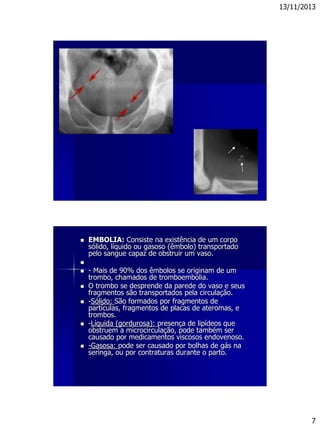

 EMBOLIA: Consiste na existência de um corpo

sólido, líquido ou gasoso (êmbolo) transportado

pelo sangue capaz de obstruir um vaso.

 - Mais de 90% dos êmbolos se originam de um

trombo, chamados de tromboembolia.

 O trombo se desprende da parede do vaso e seus

fragmentos são transportados pela circulação.

 -Sólido: São formados por fragmentos de

partículas, fragmentos de placas de ateromas, e

trombos.

 -Líquida (gordurosa): presença de lipídeos que

obstruem a microcirculação, pode também ser

causado por medicamentos viscosos endovenoso.

 -Gasosa: pode ser causado por bolhas de gás na

seringa, ou por contraturas durante o parto.